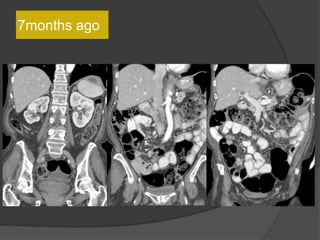

7months ago

10 months ago